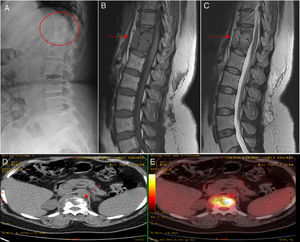

(A) The radiological study shows bone rarefaction in thoracic vertebral bodies T11 and T12, with marked erosion of their anterior borders. (B) Magnetic resonance study shows a lobulated lesion and collection affecting T11, T12 and their respective intervertebral disc (arrow), which is hypointense on a T1-weighted image. (C) Magnetic resonance study showing hyperintensity on a T2-weighted image (solid arrows). (D and E) Positron emission tomography images confirming the high metabolic activity of the lesions (broken arrows).

The patient was a 42-year-old woman with controlled intrinsic asthma, receiving chronic treatment with inhaled corticosteroids, but not requiring systemic corticosteroid therapy on a regular basis. Three years before the present consultation, she had undergone chemotherapy with isoniazid for 12 months after a positive Mantoux test, with no evidence of active disease, after being in contact with a relative who had pulmonary tuberculosis. She was admitted with a 3-month history of symptoms including mixed low back pain, with night sweats and a feverish sensation. The radiographic study revealed bone rarefaction in thoracic vertebral bodies T11 and T12, but no changes in lung parenchyma or presence of mediastinal adenopathy. Notable findings in the complementary tests were hemoglobin 11.6g/dL, erythrocyte sedimentation rate 35mm/h, C-reactive protein 1.49mg/dL (normal value<0.5mg/dL) and negative HIV test. Magnetic resonance revealed evidence of spondylodiscitis with a bilateral paravertebral and anterior epidural abscess that affected vertebral bodies T11–T12, a finding confirmed in a metabolic study carried out by positron emission tomography (Fig. 1). The microscopic study and culture of sputum, as well as blood and urine cultures, were negative, even for mycobacteria. As tuberculous spondylodiscitis (TSD) was suspected, the decision was made to perform a computed tomography-guided biopsy and begin treatment with isoniazid, rifampicin, pyrazinamide and ethambutol; analgesia with weak opioids; and the use of rigid orthosis for the lumbar spine. The histopathological study of the lesion revealed the presence of caseating granulomas suggestive of a tuberculous process, although Ziehl-Neelsen staining was negative (Fig. 2). After 12 months of antituberculous therapy, the patient's course was satisfactory, with no sequelae or limited axial mobility.